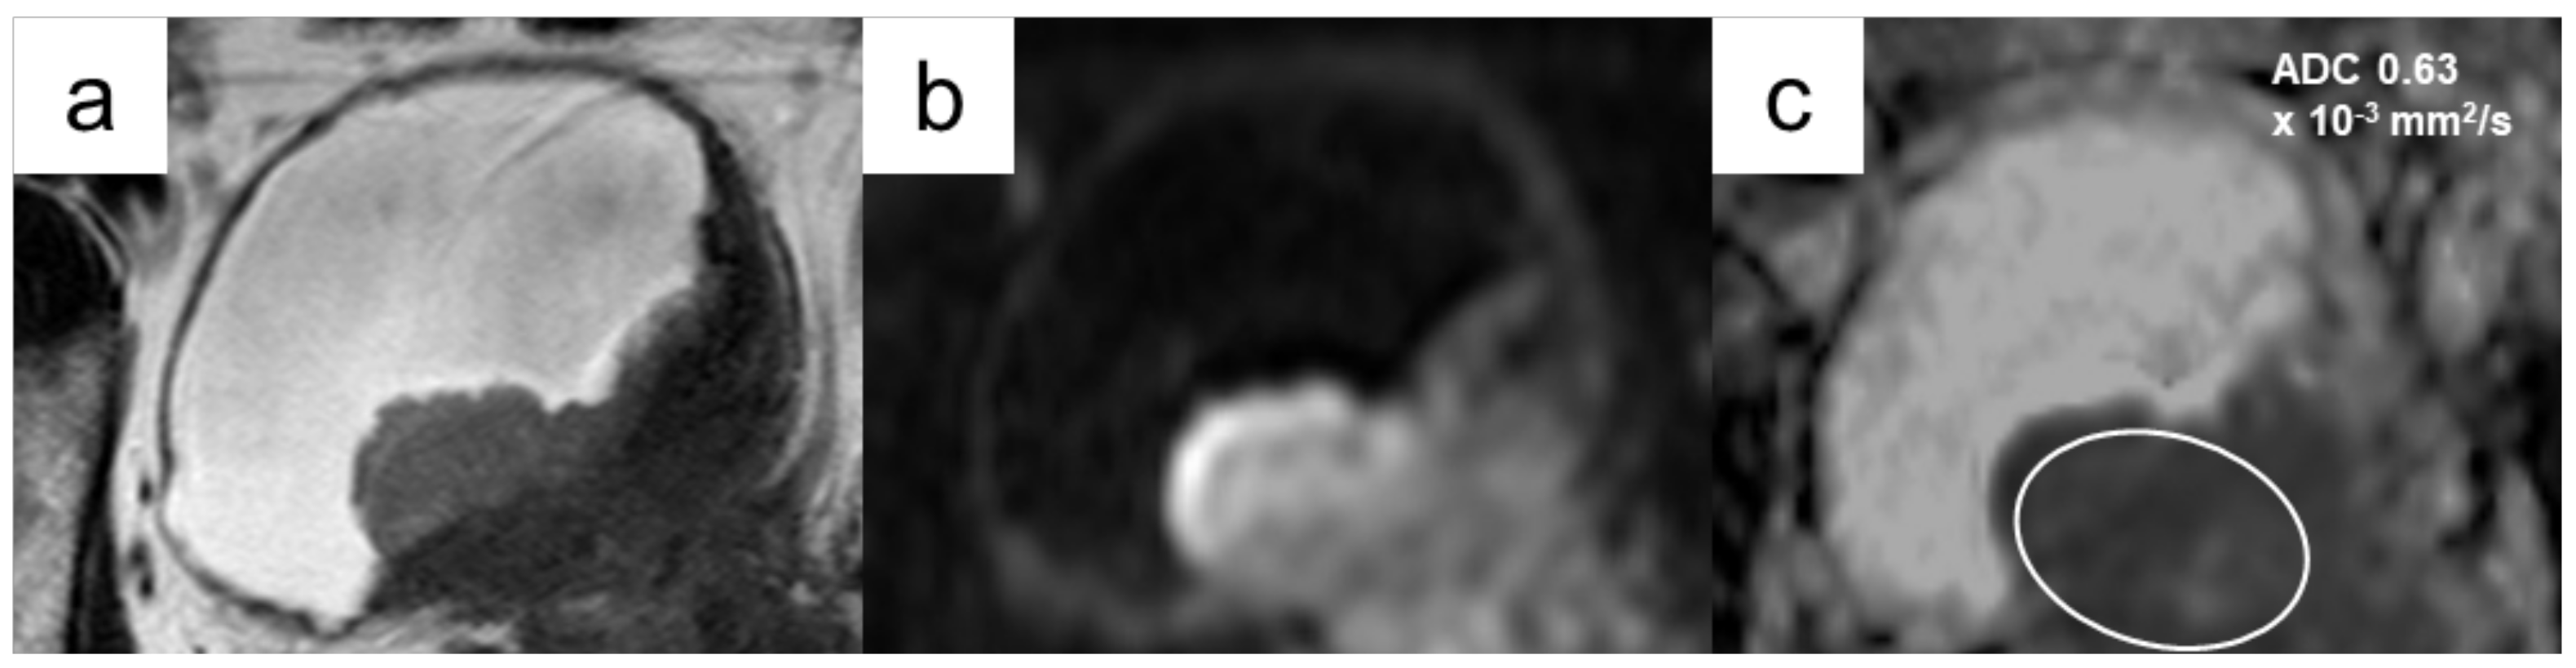

3.4.1. Diagnostic Performance of ADC Values to Differentiate MIBC from NMIBC